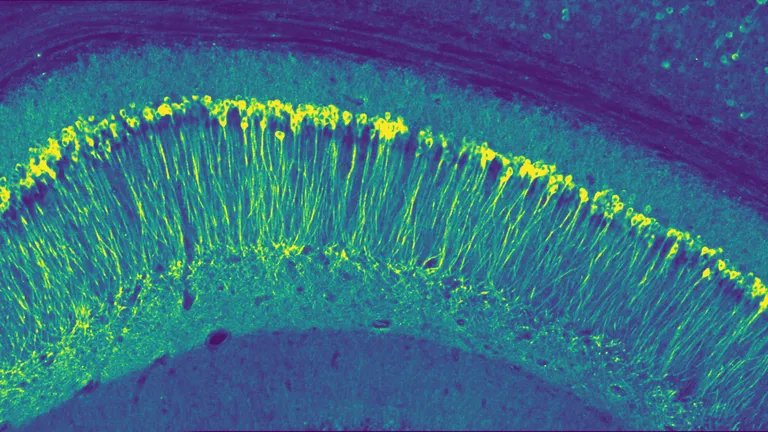

digital imagery of iPSC derived neurons